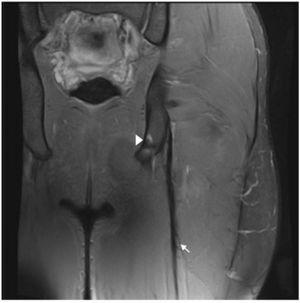

Figura 2 Las imágenes coronal y axial en T2 con saturación grasa del isquiotibilal izquierdo muestran cambios de espesor e intensidad de la señal del tendón libre (flecha), contornos borrosos y discontinuidad ampliada hasta UMT proximal. Existe retracción distal leve de UMT proximal. Vientre del músculo semitendinoso (ST), glúteo mayor (GM), tendón semimembranoso (punta de flecha) y nervio ciático (*).